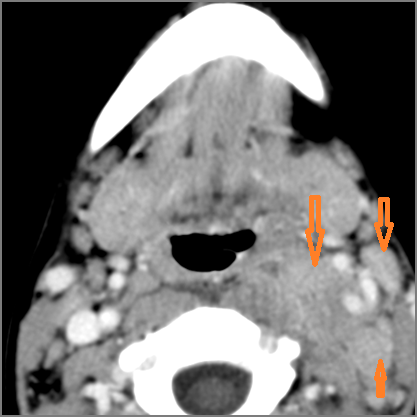

There is edema within the adjacent deep neck, retropharyngeal and/or prevertebral spaces.

There is abscess within the adjacent deep neck, retropharyngeal and/or prevertebral spaces.